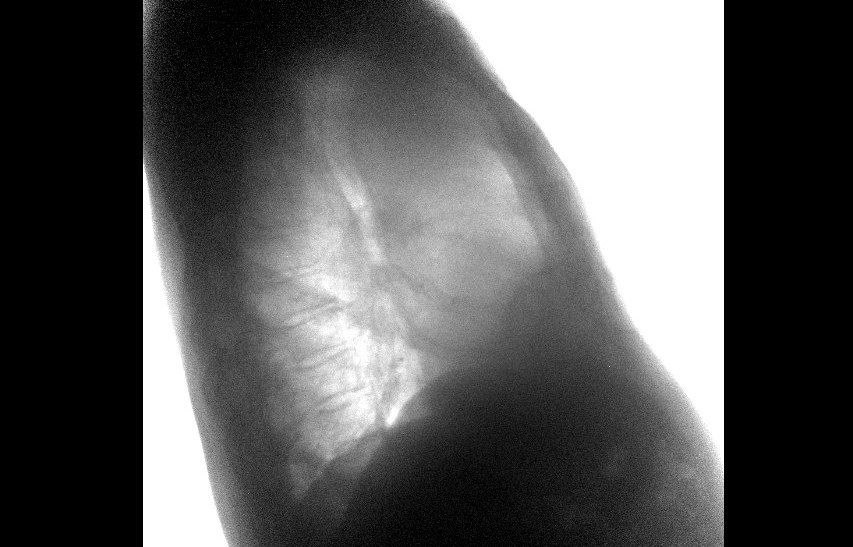

Нижегородские медики показали легкие онкобольного с 50-летним стажем курения

У жителя Нижнего Новгорода, курившего по пачке сигарет ежедневно на протяжении 50 лет, врачи обнаружили бессимптомный рак легкого. Об этом сообщает телеграм-канал "Бокал прессека".

Известно, что мужчина обратился в поликлинику №4 Канавинского района с жалобой на длительную осиплость голоса. В рамках диспансерного обследования ему была выполнена флюорография, по результатам которой врачи заподозрили наличие новообразования в легочной ткани.

Для уточнения диагноза пациенту провели компьютерную томографию, которая подтвердила наличие опухоли.